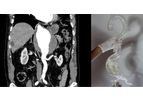

Axial3D’s vision of making patient-specific surgery routine is made possible by our software platform that automatically converts all 2D imaging currently being used in a patient's surgical care pathway into incredibly precise, clinically relevant ...

Transforming planning, diagnosis and treatment for Interventionalists, Dramatically improve patient care with our proven patient-specific solutions. Interventionalists typically rely on a patient’s CT, MRI or X-ray to aid in diagnosis and ...